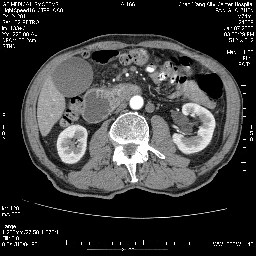

女,74岁,呕吐10余日

十二指肠水平段腔内占位伴梗阻,中等度较为均匀的强化,洗脱慢,区域淋巴结显示增多,符合腺癌表现。下腔静脉变异。

十二指肠降段扩张,水平段狭窄成鼠尾状,肠壁明显增厚,胰腺勾突增大成不均匀强化,其内可见低密度区,胆囊增大,1十二指肠水平段腺癌侵犯胰腺勾突可能大,2胰腺癌侵犯十二指肠(只有胆囊增大没有肝内外胆管扩张不好解释)代除外.

上消化道造影见十二指肠结节状充盈缺损,ct增强十二指肠壁局限性增厚并强化,考虑十二指肠壶腹癌?

十二指肠降段扩张,水平段狭窄成鼠尾状,肠壁明显增厚,胰腺勾突增大成不均匀强化,其内可见低密度区,胆囊增大,1十二指肠水平段腺癌侵犯胰腺勾突可能大,2胰腺癌侵犯十二指肠 。

今日手术结果:胰腺钩突癌侵犯十二直肠,腹腔淋巴结转移.